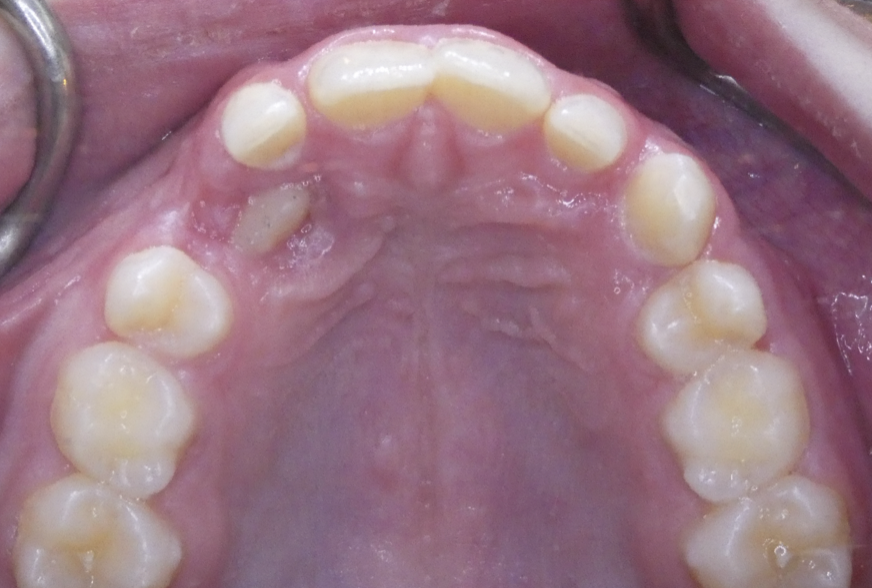

Crowding

Lack of space causes crowding as teeth erupt.